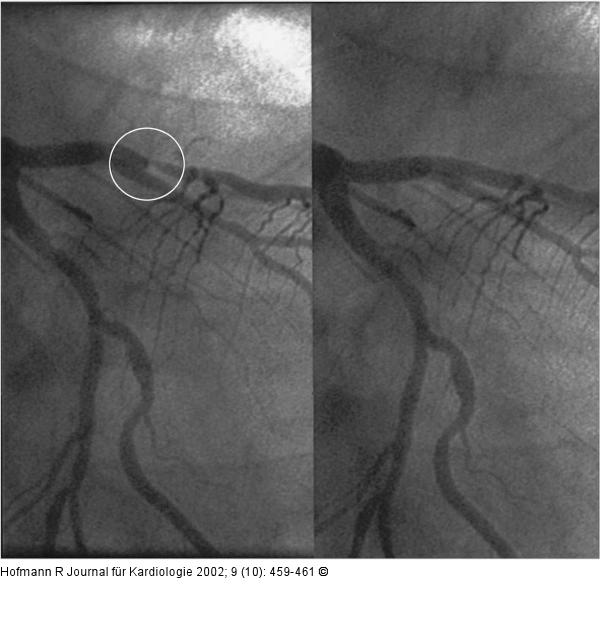

Abbildung 4: ST-Hebung nach Thalliumszintigraphie Angiogramm der linken Koronararterie: hochgradige Stenose im Ramus interventricularis anterior (Kreis). Links vor, rechts nach Stentimplantation. |

Angiogramm der linken Koronararterie: hochgradige Stenose im Ramus interventricularis anterior (Kreis). Links vor, rechts nach Stentimplantation. |